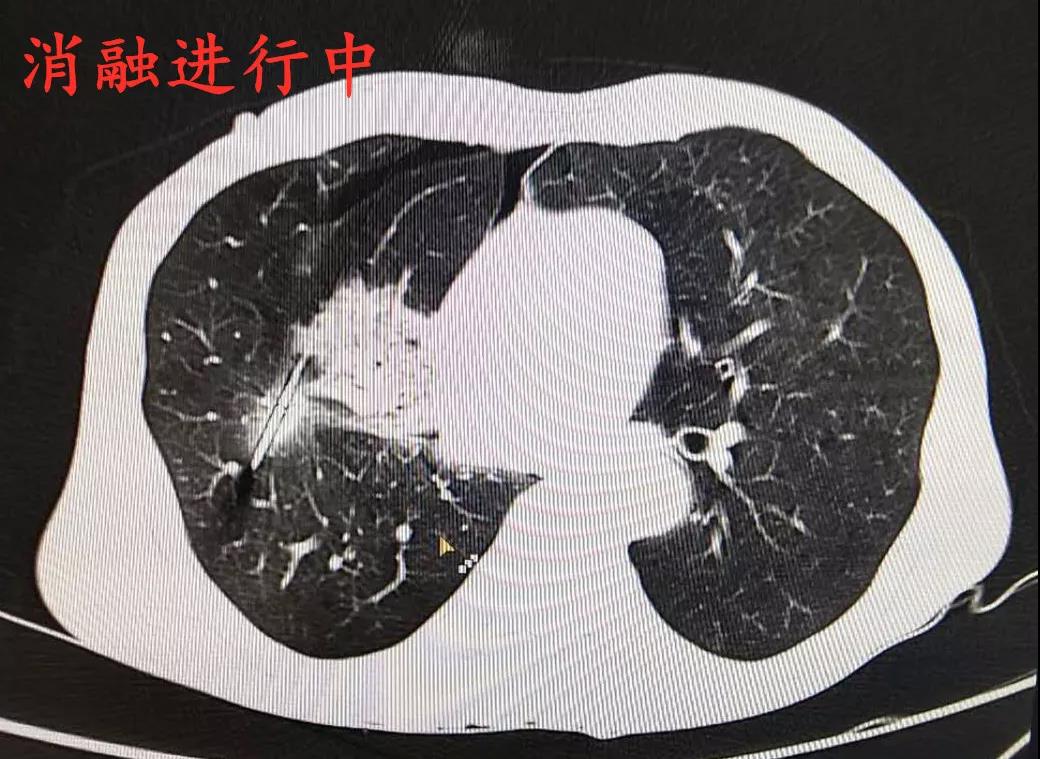

手术在CT室进行,在福建医科大学附属第一医院介入科林征宇主任的指导下,郑主任带领的胸外科团队首先对患者肺结节在CT下做了精确定位,然后使用直径仅为3mm的电极针穿刺至结节位置,给电极针提供电流,使其产生高频电磁场致局部产热,从而使结节细胞发生凝固性坏死。整个手术在局麻下完成,射频过程患约15分钟,无切口、患者无明显不良反应,无手术痛苦,术后几小时患者即可自由活动,无不适症状发生。